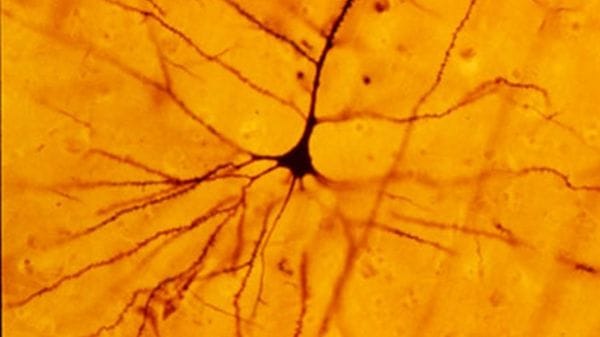

Dalla scoperta dei cosiddetti neuroni specchio , che si attivano sia quando compiamo un'azione sia quando la osserviamo fare a qualcun altro, agli studi che hanno fatto luce sulla malattia di Huntington , un raro disturbo genetico neurodegenerativo per il …